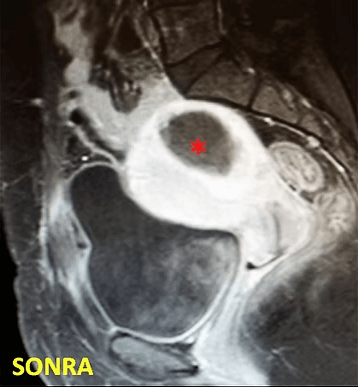

41 yaşında, kabızlık, gaz ve sık idrara çıkma şikayetleri var. Emar’da karını dolduran dev miyom (*) mevcut. Miyomektomi önerilmiş, ancak operasyonda rahimin alınabileceği söylenmiş. Embolizasyondan sonra dev miyomun ve bir başka küçük miyomun öldüğü ve küçüldüğü izleniyor. 7 ay sonra hasta şikayeti kalmamıştır.